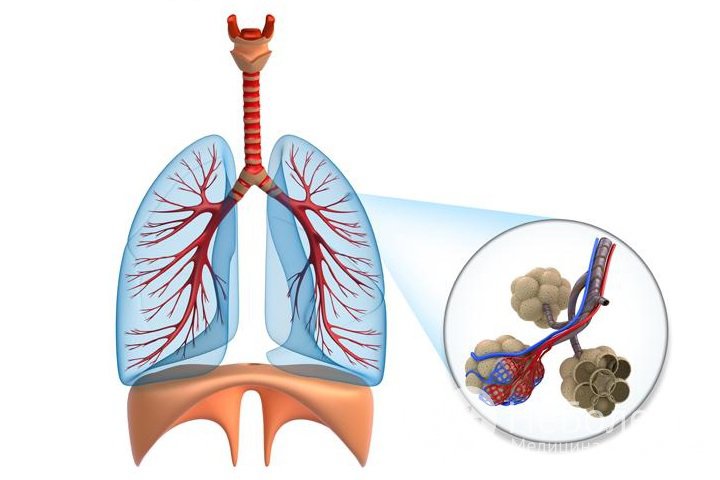

Идиопатический фиброзирующий альвеолит (синдром Хэммена – Рича, интерстициальный диффузный пневмофиброз, фиброзная дисплазия легких, синдром Скеддинга) – пульмонологическое заболевание, для которого характерно диффузное поражение интерстициальной ткани легких, приводящее к развитию пневмосклероза, легочного сердца и дыхательной недостаточности.

Идиопатический фиброзирующий альвеолит – диффузное поражение интерстициальной ткани легких

Идиопатический фиброзирующий альвеолит – диффузное поражение интерстициальной ткани легкихВ патологическом механизме выделяется несколько взаимосвязанных между собой процессов:

- отек интерстициальной ткани;

- альвеолит (воспаление альвеол);

- интерстициальный фиброз.